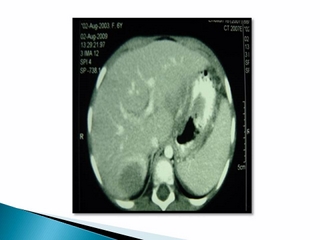

لنفوم-Lymphoma

دکتر رکسانا ازما

فوق تخصص رادیولوژیست